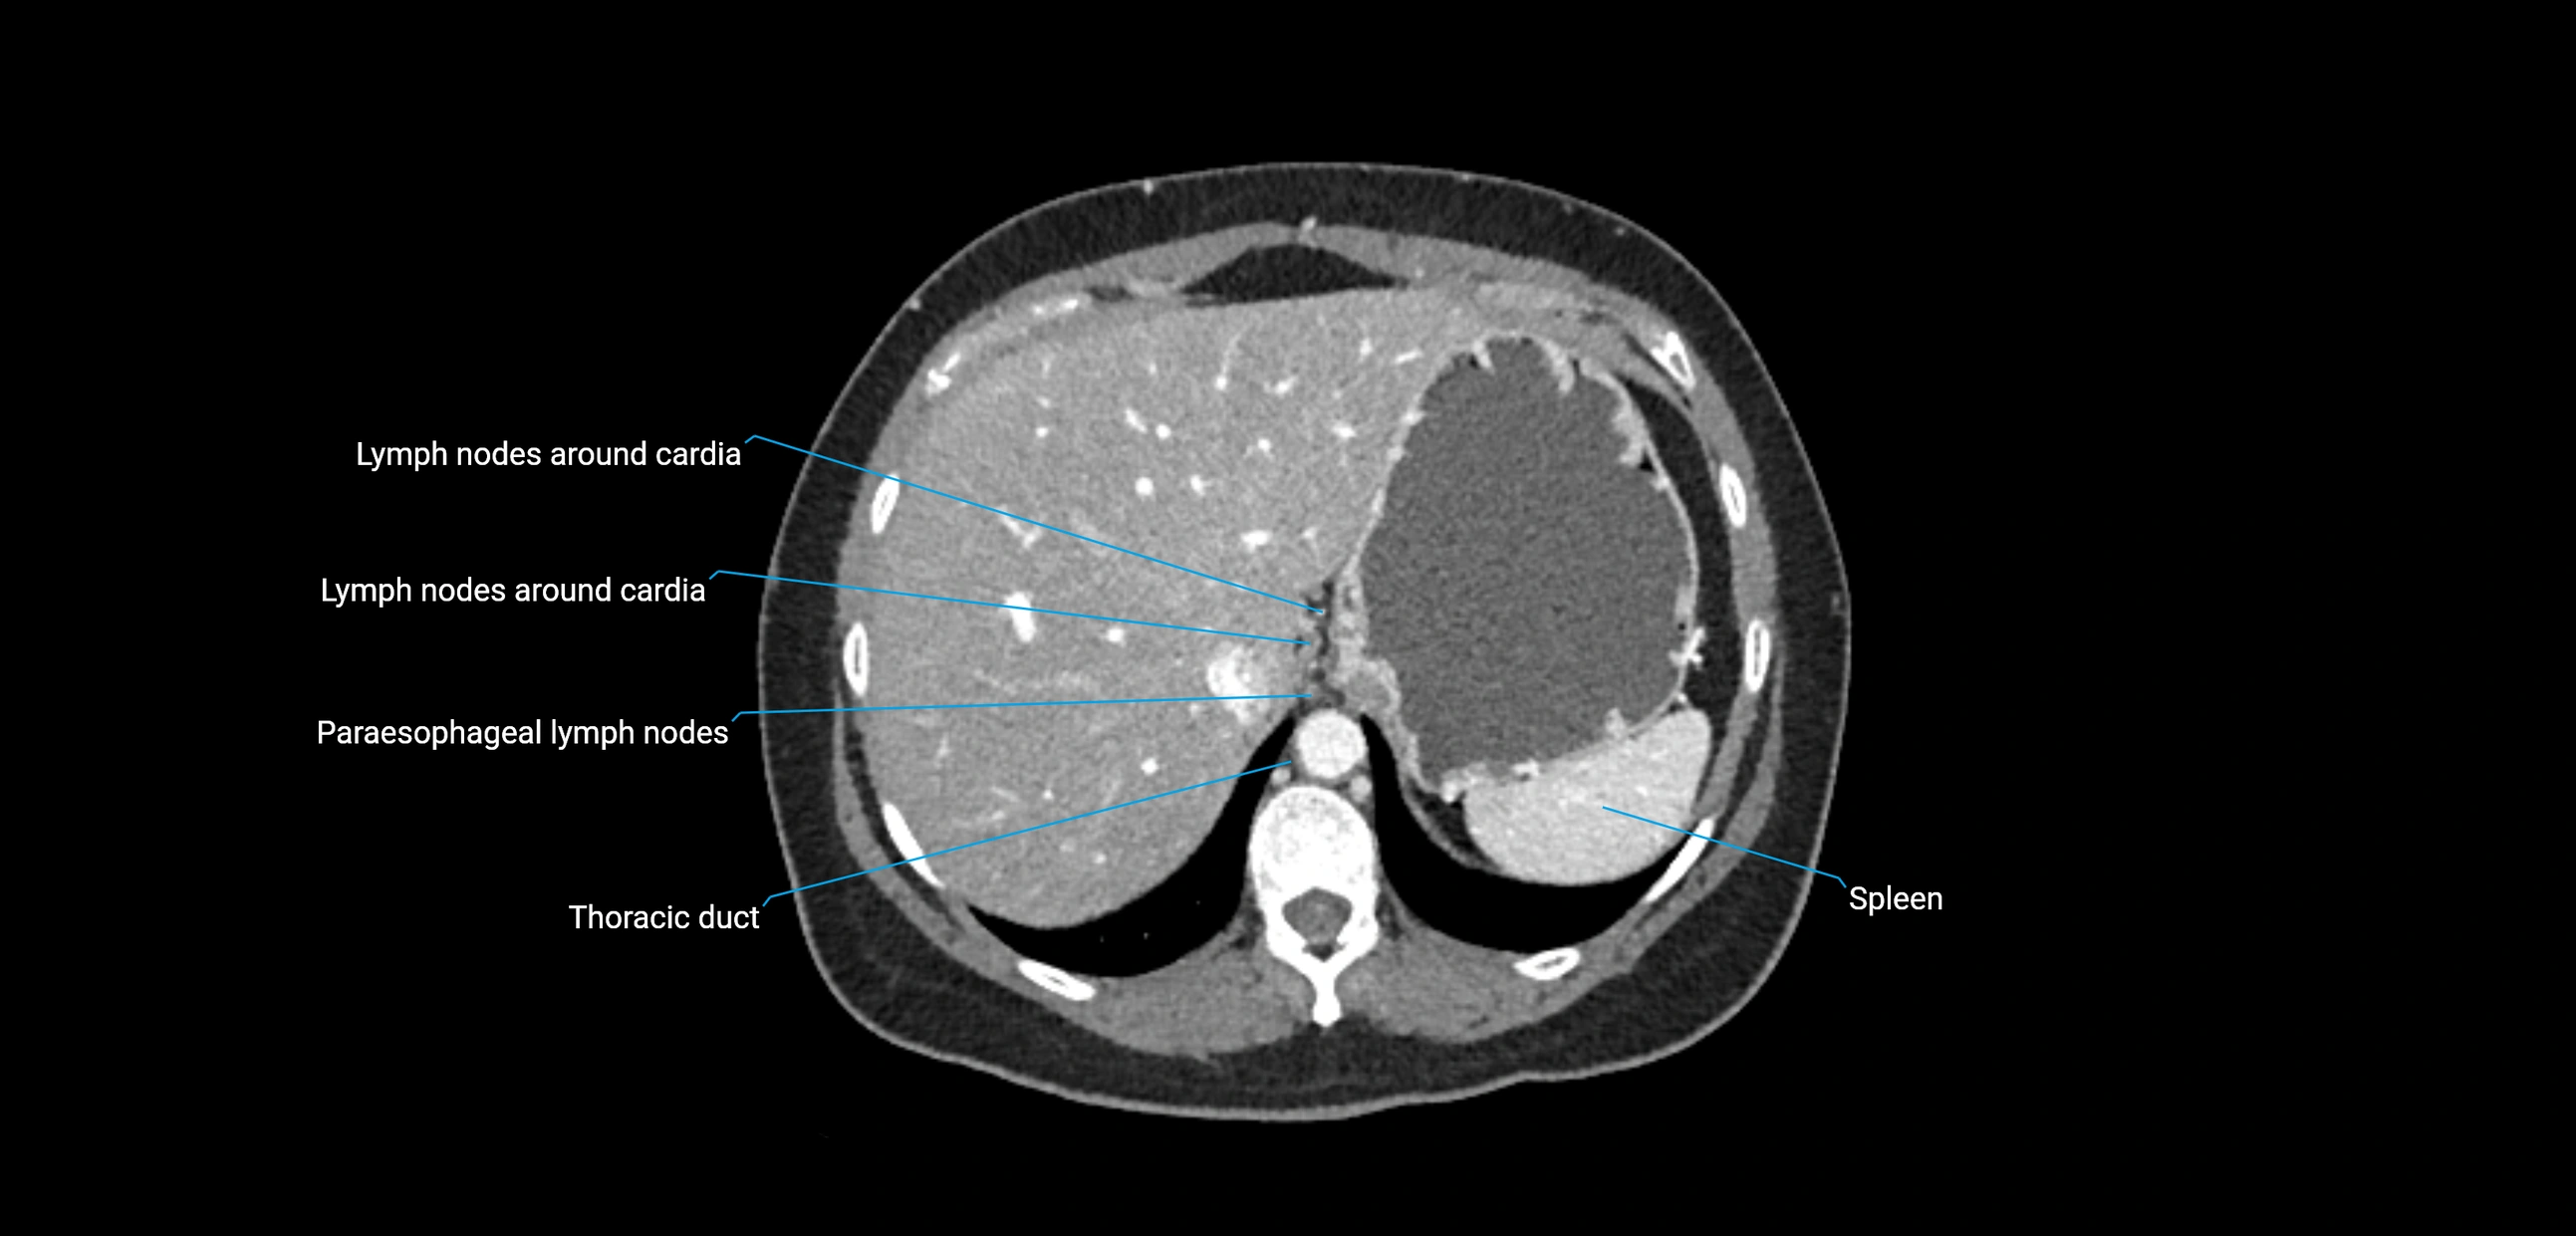

CT Appearance

CT Pre-Contrast:

• Nodes appear as soft-tissue density nodules adjacent to the aorta and IVC

CT Post-Contrast:

• Normal nodes enhance homogeneously

• Malignant nodes may show heterogeneous enhancement, central necrosis, or conglomerate formation

• Size >1 cm short axis is suspicious, though morphology and distribution are equally important